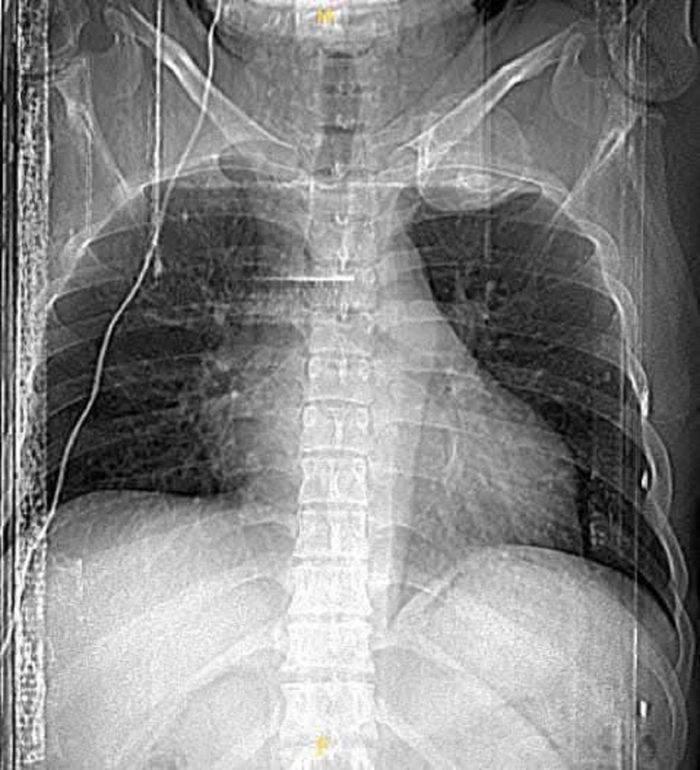

Kết quả chụp cắt lớp vi tính ngực cho thấy hình ảnh khối u cung sau xương sườn số 1 kích thước 5x6cm, choán gần toàn bộ vùng hõm đỉnh.

Kết quả chụp cắt lớp vi tính ngực cho thấy hình ảnh khối u cung sau xương sườn số 1 kích thước 5x6cm, choán gần toàn bộ vùng hõm đỉnh bên trái, mặt trước của khối u dính sát phía sau động mạch, tĩnh mạch dưới đòn trái, bờ trên và sau của khối u nằm sát đám rối cánh tay, bờ dưới của khối u dính vào đỉnh phổi trái.

Hình ảnh phim chụp của bệnh nhân.

Hình ảnh u cung sau xương sườn số 1 trên phim chụp của bệnh nhân.